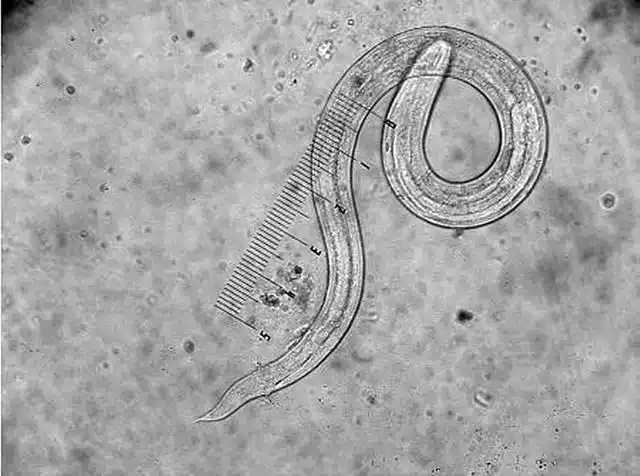

经过检查后,医生告诉小慕,孩子的下身出现瘙痒是因为蛲虫病,所以孩子